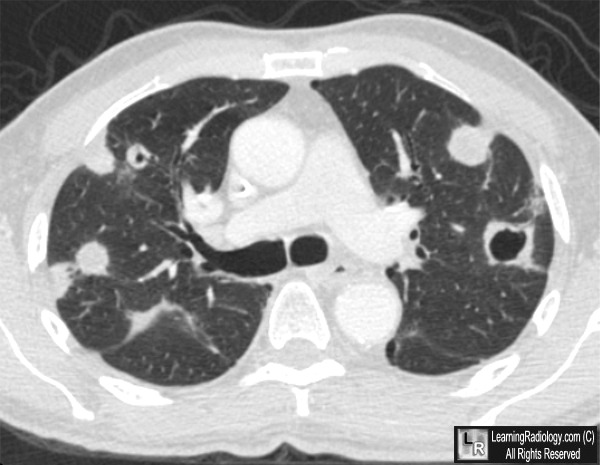

Cavitary Metastases to the Lung. Frontal and lateral chest radiograph (above) show multiple masses

in both lungs. At least one mass in the left lung (white arrow) is seen to be cavitary. An axial CT scan of the same patient demonstrates multiple masses, two of which show obvious cavitation (white arrows).